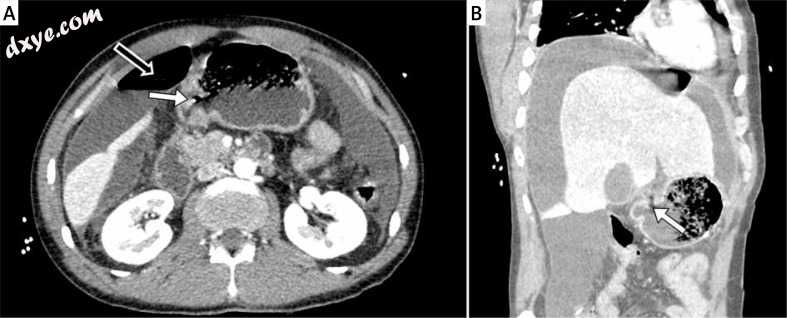

照片1

术前腹部CT扫描穿孔十二指肠溃疡。 A-轴向腹部CT扫描显示十二指肠第一部分的壁穿孔(白色箭头)和气腹(黑色箭头)的存在,B  - 冠状位腹部CT扫描显示穿孔位于第一部分的前表面 十二指肠(白色箭头)